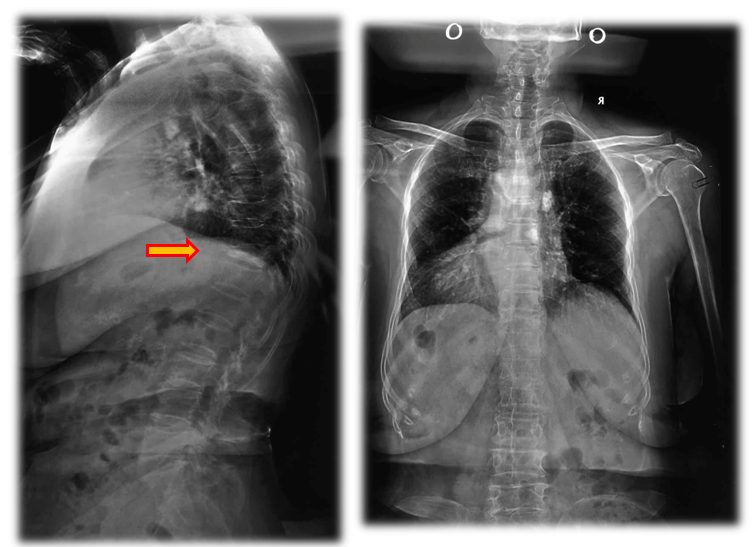

术前X线

术前检查

俯卧过伸位片

术前诊断:骨质疏松症,Kummell病。

术后影像学

术后检查

术后X线

术前后侧位

术后3月X光